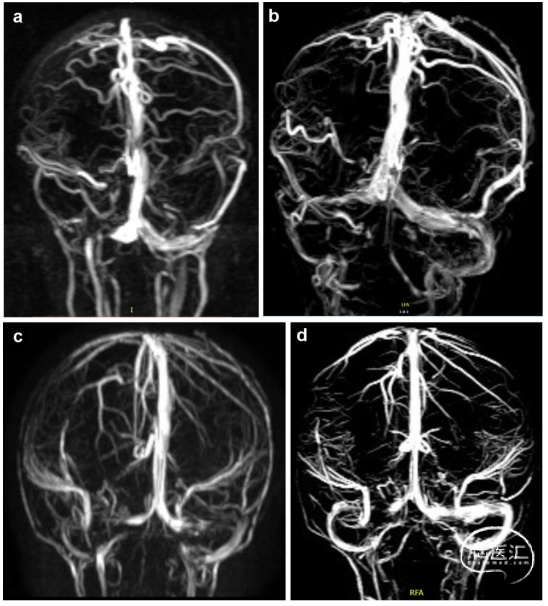

硬脑膜静脉窦解剖变异分级随年龄增大而改变,7例患儿在最后一次PC-MRV静脉分级与初步诊断时一致,5例患儿的闭塞或狭窄改善,6例加重(图4)。

图4. 硬脑膜静脉窦变异分级随年龄改变。a.11个月M/WSS女婴。PC-MRV显示,右侧横窦近端1/3明显血流中断(2B级)。b.与a图同一患儿6岁6个月时,PC-MRV显示,右侧横窦发育不全(0级)。c.9个月M/WSS男婴。PC-MRV显示双侧横窦的血流中断(4A级)。d.为c图同一患儿13个月后PC-MRV显示右侧横窦的血流中断仍明显,但左侧横窦大小和血流均有所改善(2B级)。